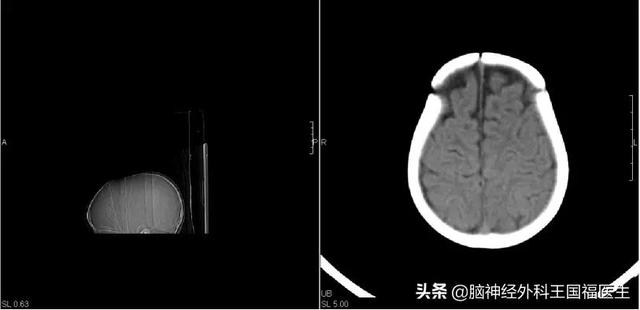

很快就为这位小朋友安排了手术,手术通过大面积松解颅骨解除对脑组织的压迫。

这是术后颅骨CT重建的影像

术后小刚复查虽然还有癫痫波存在,但脑电异常的频率和位点已经明显减少,只用服用最低剂量的抗癫痫药物就能完全控制不发作,这只是术后3个月的复查结果,毕竟病情是一步一步好转的,远期的效果目前还在观察之中。